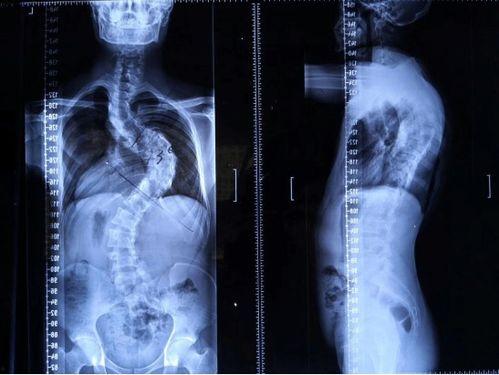

脊柱矫正,顾名思义,就是通过各种方法来调整脊柱的形态,使其恢复到正常状态。这个过程可能涉及到物理治疗、按摩、针灸、手术等多种手段。那么,成人还能矫正脊柱吗?答案是肯定的!

脊柱矫正的原理其实很简单,就是通过外力来改变脊柱的受力点,从而逐步调整脊柱的形态。这个过程需要耐心和毅力,因为脊柱矫正并非一蹴而就的事情。

脊柱矫正的效果因人而异,但一般来说,经过一段时间的治疗,大部分患者的脊柱都会得到明显改善。具体效果如下:

1. 缓解疼痛:脊柱矫正可以缓解因脊柱弯曲引起的疼痛。

2. 改善姿势:脊柱矫正可以帮助改善不良的姿势,使身体更加挺拔。

3. 提高生活质量:脊柱矫正可以改善患者的睡眠质量,提高生活质量。